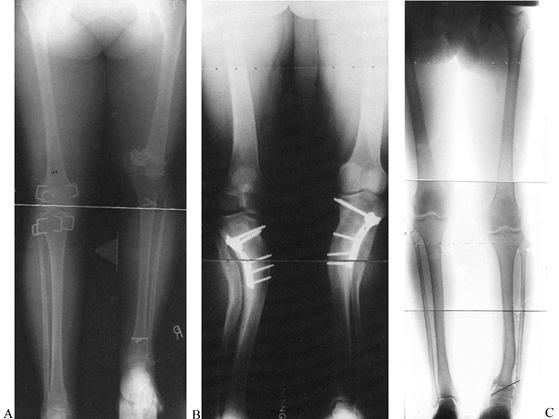

![]() |

Figure 32.19. A: Juxtaarticular tibial deformity with a normal femur. Step 0:

Draw the mechanical axis line from the center of the femoral head to the center of the ankle. The malalignment test was performed to confirm that the varus mechanical axis deviation is due only to the tibia and that the femur is normal. Step 1: Draw the mechanical axis line of the femur and extend it distally. This is the mechanical axis of the proximal tibia. Step 2: Draw the line from the center of the ankle plafond extending proximally parallel to the anatomic axis of the tibia. This is the mechanical axis of the distal tibia. Note that the level of intersection of the two mechanical axis lines is at the level of the growth plate. The angular deformity measures 37°. Step 3A: The deformity may be corrected by a 37° opening wedge through the growth plate, thus realigning the mechanical axis and reestablishing normal joint orientation. Step 3B: Correction of the deformity at the level of the tibial metaphysis requires a 50° correction to realign the mechanical axis. This creates a malorientation of the knee and ankle. Notice that the mechanical axis now subtends a 96° orientation to the ankle joint instead of the normal 90°. Step 3C: If only 37° of deformity is corrected, then there is persistent varus mechanical axis deviation. The knee and ankle are oriented correctly to each other, but the mechanical axis is deviated due to a persistent translational deformity (T). Step 3D: To realign the mechanical axis at the level of the metaphysis, which is distal to the apex of the deformity, the correction should include both 37° of angular correction and lateral translation in the amount of T. The magnitude of T increases as the level of the osteotomy moves farther away from the apex of the deformity. B: If the hinge is placed at the level of the osteotomy, overcorrection is required to eliminate mechanical axis deviation. Note that the rings are not parallel at the end of correction because of overcorrection. C: The apparatus is preconstructed with the hinge at the level of the center of rotation of angulation. This leads to angulation and translation. The rings are parallel at the end of correction. |